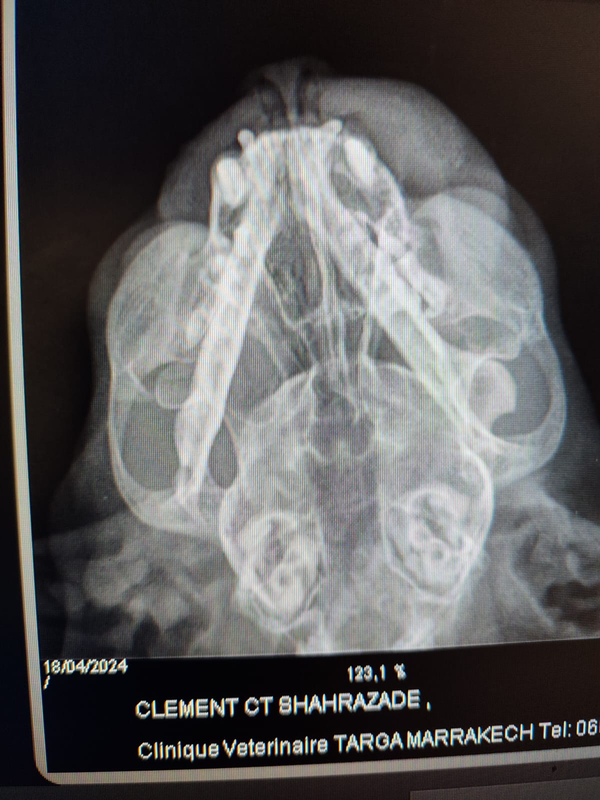

On m'annonce que la tumeur de Schéhérazade est cancéreuse, que l'os et visiblement légèrement touché, sur cette radio. La radio est montrée à un professeur de l'école vétérinaire de Rabat, pour qui cette tumeur est opérable. L'os pourrait être gratté. Nous avons l'obligation de séjourner dans une ville dans laquelle les soins vétérinaires pour les chats sont très peu développés. Il ne serait donc pas possible d'y assurer des soins post opératoires. Nous devons attendre pour effectuer la chirurgie avec des soins nécessaires ensuite. D-s mon retour en France, que j'espère le plus tôt possible, l'opportunité de radiothérapie ou de chimiothérapie doit être recherchée.